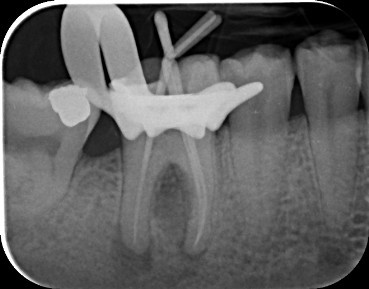

Case 1: Root Canal Treatment UR5